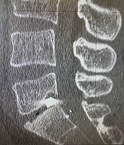

Пациент П., 05.05.2025 г. при взрыве снаряда получил слепое проникающее в позвоночный канал осколочное ранение пояснично-крестцового отдела позвоночника. В течение двух месяцев пациенту оказывалось консервативное лечение. 13.07.2025 г. пациент поступил на лечение в ГВКГ им. ак. Н.Н. Бурденко. При обследовании на КТ выявлен осколок металлической плотности в межтеловом промежутке по срединной линии у заднего края тел на уровне пятого поясничного и первого крестцового позвонков. Осколок прошел через междужковый промежуток сзади по краю фасеточного сустава. У больного имелась клиника болевого синдрома в пояснично-крестцовом отделе позвоночника во время движений и парестезий в проекции S1 корешка. Силовых расстройств не было.

Рис. 1 КТ-картина расположения осколка в трех проекциях.